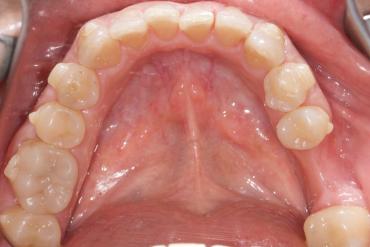

State before orthodontic treatment — in the case of large crowding of teeth, it is not recommended to perform IPR immediately due to the difficult access to the tangent space of the teeth.